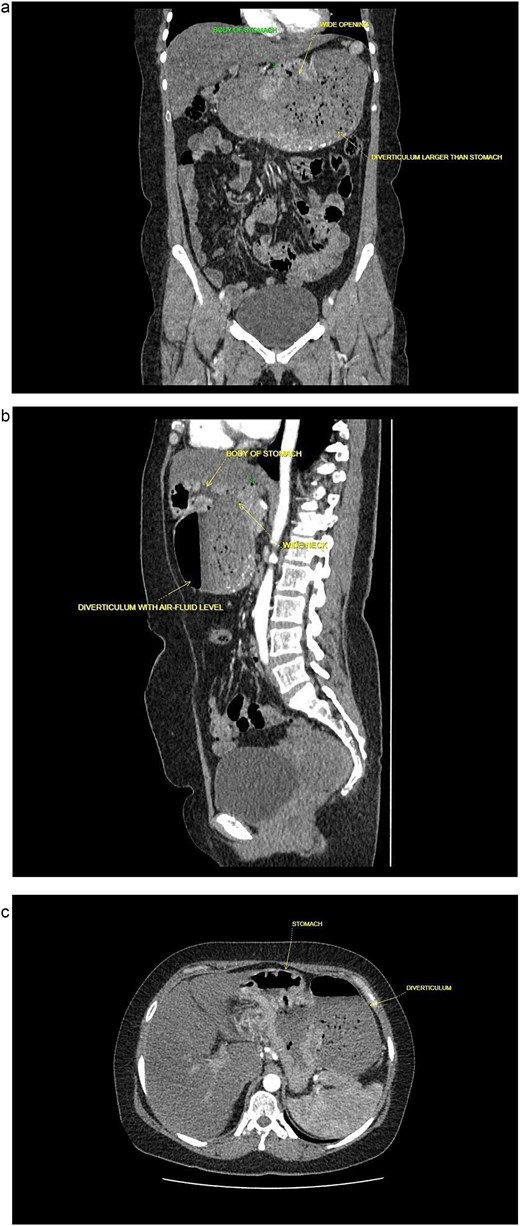

A 40-year-old postmenopausal female, known to have rheumatoid arthritis and type 2 diabetes mellitus, presented with persistent postprandial vomiting for 2 months, associated with abdominal fullness and weight loss (17 kg over 5 years). On physical examination, the patient was ill-looking but afebrile and haemodynamically stable. The abdomen was soft and non-tender, with mild epigastric fullness and no palpable mass. The timeline of clinical events from presentation to follow-up is shown in Table 1. Initial upper gastrointestinal endoscopy revealed retained food particles suggestive of gastric outlet obstruction. Ultrasonography was inconclusive. Contrast-enhanced CT of the abdomen and pelvis showed a large posteriorly located cystic lesion (18 × 11 × 12 cm) with internal debris, initially interpreted as a giant gastric diverticulum compressing adjacent structures (Fig. 1a–c).

Contrast enhanced computed tomography (CECT) of abdomen and pelvis. (a) Sagittal plane. (b) Coronal plane. (c) Axial plane.